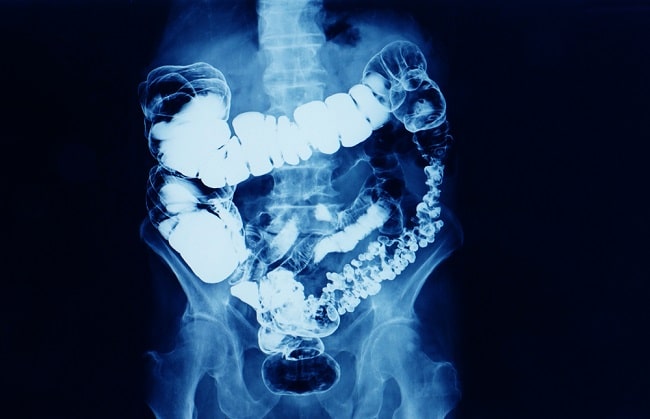

Gambar 1. Hasil Barium Enema X-ray.

Barium enema X-ray adalah pemeriksaan radiologi menggunakan kontras tunggal maupun ganda untuk mengevaluasi kolon, misalnya pada penyakit divertikular, fistula kolon, kanker kolorektal, dan kegagalan kolonoskopi. Tujuan pemeriksaan ini adalah untuk memvisualisasikan kolon dengan berbagai sudut pandang dan dengan dosis radiasi seminimal mungkin.[1]

Barium enema diindikasikan untuk memeriksa karakteristik struktural dan fungsional saluran cerna bawah, seperti menegakkan diagnosis nyeri perut, perubahan bowel habit, dan penurunan berat badan yang tidak diketahui sebabnya. Pemeriksaan ini juga dapat mengevaluasi penyebab perdarahan saluran cerna, seperti kanker kolorektal, divertikulitis, dan inflammatory bowel disease.[2–4]